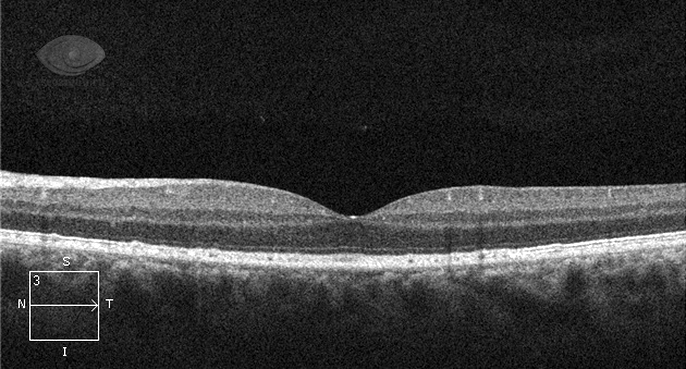

- Оптическая когерентная томография позволяет получать изображения всех слоев макулярной области с высокой точностью.

Современные технологии, такие как оптическая когерентная томография (ОКТ), позволяют более точно диагностировать заболевания макулы и отслеживать их прогрессирование, что способствует более эффективному лечению.